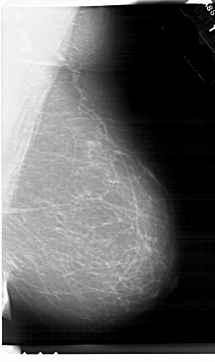

A_1665_1.RIGHT_MLO

RIGHT_MLO LINES 6871 PIXELS_PER_LINE 4081 BITS_PER_PIXEL 12 RESOLUTION 43.5 NON_OVERLAY